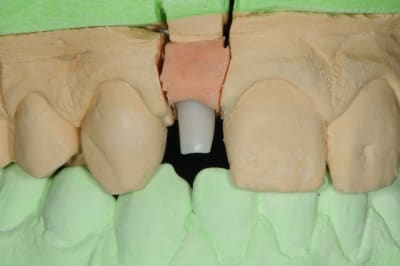

01/09/2010 à 16h54

-1 ou 2 mois plus tard ( je sais plus)

- empreinte avec transfert pop in

- pilier zircone esthétique Axiom

- prothèse et pilier

- pilier zircone en place

- couronne en place (petite compression gingivale)

fin du traitement